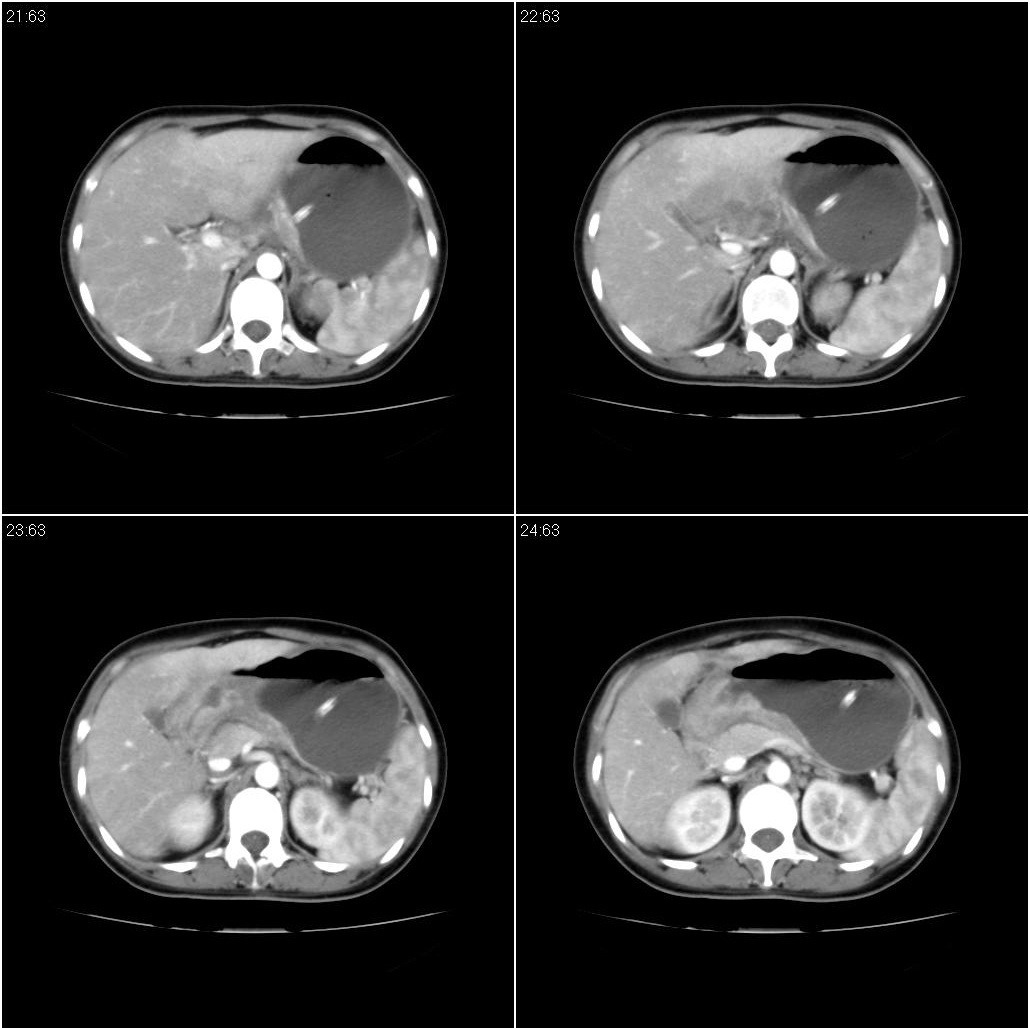

标题: CT21386:女性,33岁。4个月前因妊娠发现盆腔肿物。 [打印本页]

女性,33岁。4个月前因妊娠发现盆腔肿物。ca-125: 1100

胃幽门部癌伴小弯侧和腹腔淋巴结转移,胃内有胃管。

有明显淋巴结吗?我们感觉像是胰腺和胃窦。不过,胰腺尤其是胰头较大,不知道是否正常?

胃窦贲门胃小弯好像都厚啊 ,胃窦处比较明显,而且胃腔扩张明显,考虑胃癌伴梗阻。

胃壁局限性增厚,支持肿瘤性病变伴周围脓肿形成可能

未见明显肿大淋巴结,另肝脾大

支持;胃癌【浸润】幽门梗阻.胰头、胆囊及肝左叶受侵,副脾.